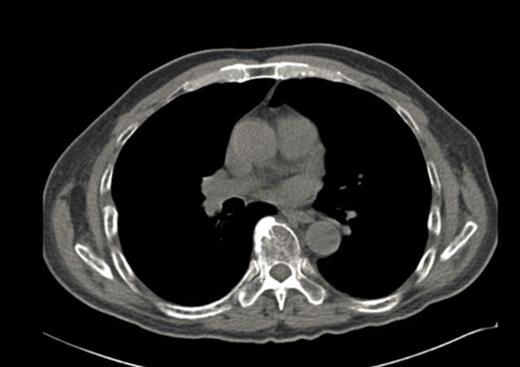

A 64-year-old male with chronic low back pain presented to the emergency department with new onset severe mid back pain radiating to bilateral shoulders. CT scan, performed to rule out aortic dissection, demonstrated multiple lytic lesions throughout the bony skeleton and a compression fracture at T7 vertebral body with epidural extension of soft tissue. A bone survey confirmed CT scan findings, and subsequent bone marrow biopsy confirmed the diagnosis of MM. He received radiation therapy to the thoracic spine and completed 2 cycles of CyBorD regimen (Cyclophosphamide 300 mg/m2 by mouth, BTZ 1.5 mg/m2 sub-cutaneous, and Dexamethasone 40 mg by mouth each on day 1, 8, 15 and 22). Three days after the completion of the second cycle, he was admitted to hospital with respiratory distress. CT chest (Image 2) showed new interval appearance of bilateral perihilar groundglass opacities, peribronchial and interstitial thickening predominantly in the upper lobes not seen in prior scan (Image 1). There were no other signs or symptoms of pneumonia such as leukocytosis, fever or cough. After some benefit from oral prednisone, he was discharged with a tapering dose of the same. Unfortunately, patient was readmitted with worsening respiratory distress 4 days later. A repeat CT scan of the chest showed resolution of previously well-defined areas of perihilar ground glass opacities but development of hazy areas of ground-glass opacification throughout both lungs with more confluent abnormalities in bilateral lower lobes (Image 3). Patient was treated with high dose methyl-prednisone and noninvasive positive pressure ventilation without any improvement. Family requested do-not-resuscitate and do-not-intubate status. Patient died on 10th day of the admission.